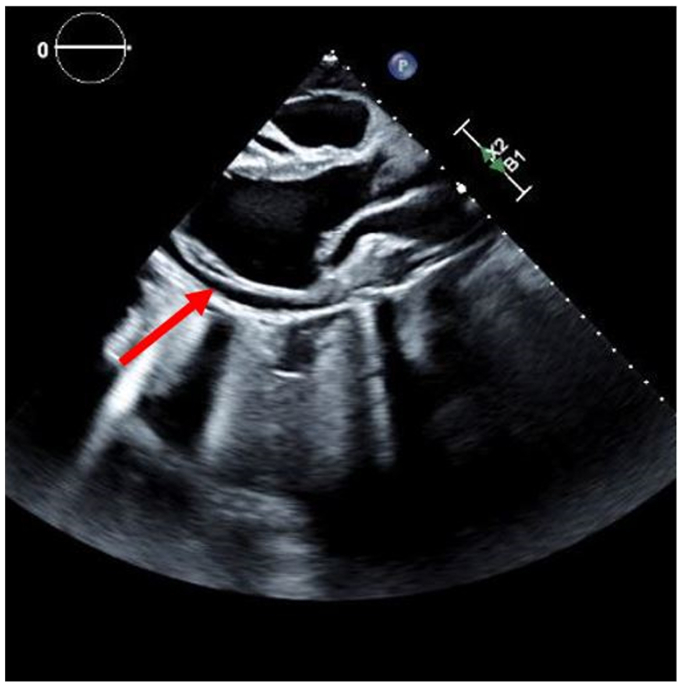

Ten days after discharge, the patient was readmitted with symptomatic pericardial effusion identified on echocardiogram (Fig 5). He underwent a pericardial window with fluid and tissue analysis confirming reactive etiology. He has since recovered appropriately. Follow-up CTA confirmed stable TEVAR and PA pseudoaneurysm coiling.

Fig 5.

Transthoracic echocardiogram revealed a moderate to large pericardial effusion identified with a red arrow.